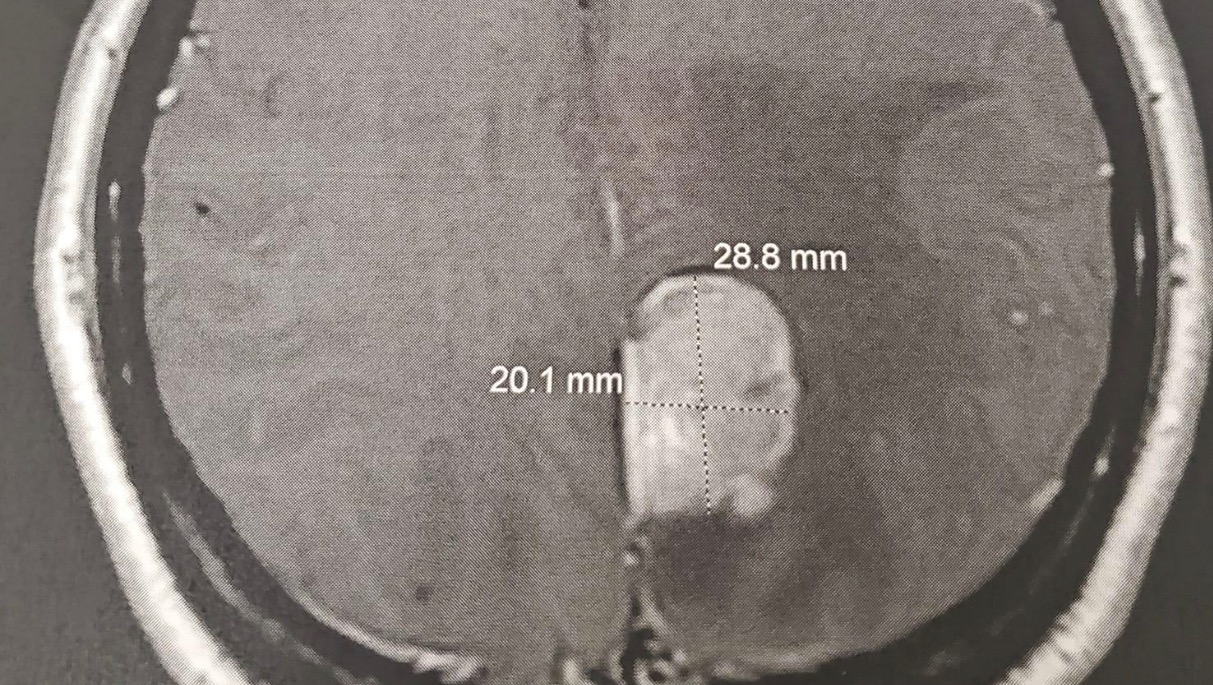

Donna beat breast cancer once and just received word that there is a mass snuggled up in her brain (the picture is below). As a wife, mom, friend and SURVIVOR, she has been through more struggles than some twice her age. Yet - she greets every day with a smile and a sense of humor - she has named the tumor and is focused on his eviction.

Her surgery is on Tuesday, Aug. 10, where they will remove the mass and see if the breast cancer has metastasized and create a go-forward treatment plan. You can read more from her on her Facebook page: https://www.facebook.com/donna.b.inglis